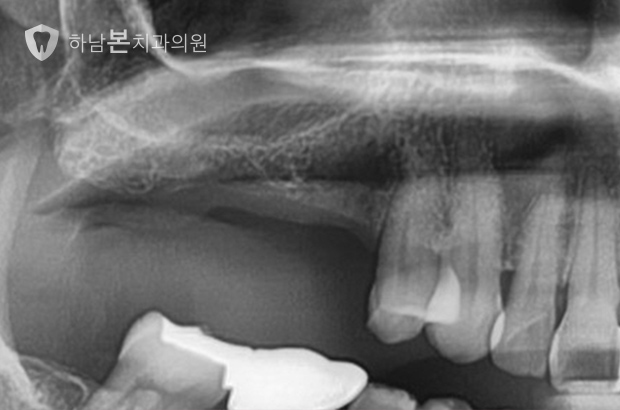

뼈이식 임플란트 케이스

CASE 1 / 상악 오른쪽 대구치 3개 / 상악동 뼈이식 임플란트